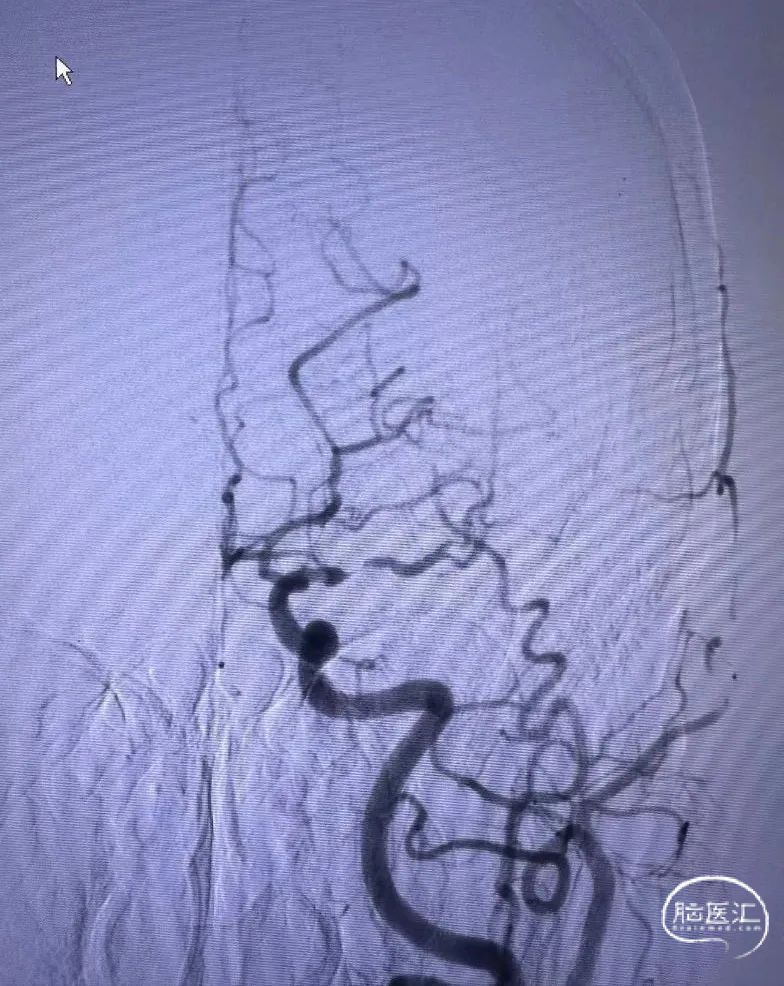

➤2024.3.2 DSA

左侧大脑中动脉M1段重度狭窄。

➤经股动脉入路造影影像

II型弓,左侧大脑中动脉M1段重度狭窄(几近闭塞)。